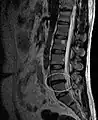

L'imagerie par résonance magnétique peut montrer la hernie, le canal vertébral, les nerfs, les tissus environnants. Les tissus mous sont les mieux analysés par cet examen qui est le plus performant pour le diagnostic de hernie discale. Les images pondérées en T2 montrent clairement la hernie.

IRM lombosacrée sagittale montrant une hernie discale de niveau L4-L5.

IRM lombaire sagittale montrant une hernie discale de niveau L4-L5.

IRM lombaire sagittale montrant une hernie discale de niveau L4-L5.- IRM lombaire sagittale montrant des protrusions discales.